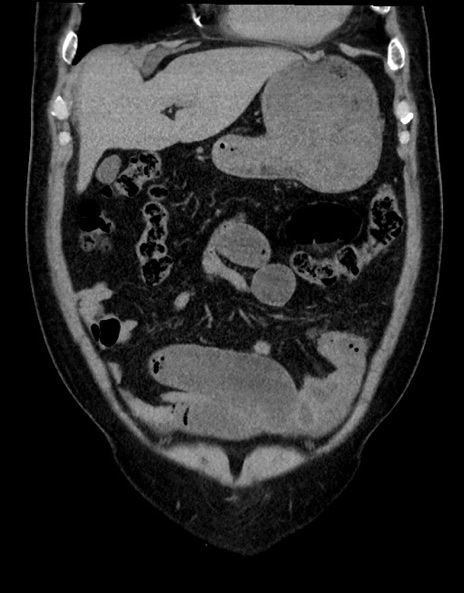

症例15(冠状断像)

【症例】70歳代男性

【主訴】腹痛

【現病歴】今朝から腹痛あり。全体的に痛い。特に左上の方。排ガスが今日はない。冷や汗が出る。

【既往歴】直腸癌術後

【身体所見】左側腹部〜上腹部に圧痛あり。腹膜刺激症状明らかなではない。軽度反跳痛。左下腹部に術後瘢痕あり。

【データ】WBC 7700、CRP 0.02